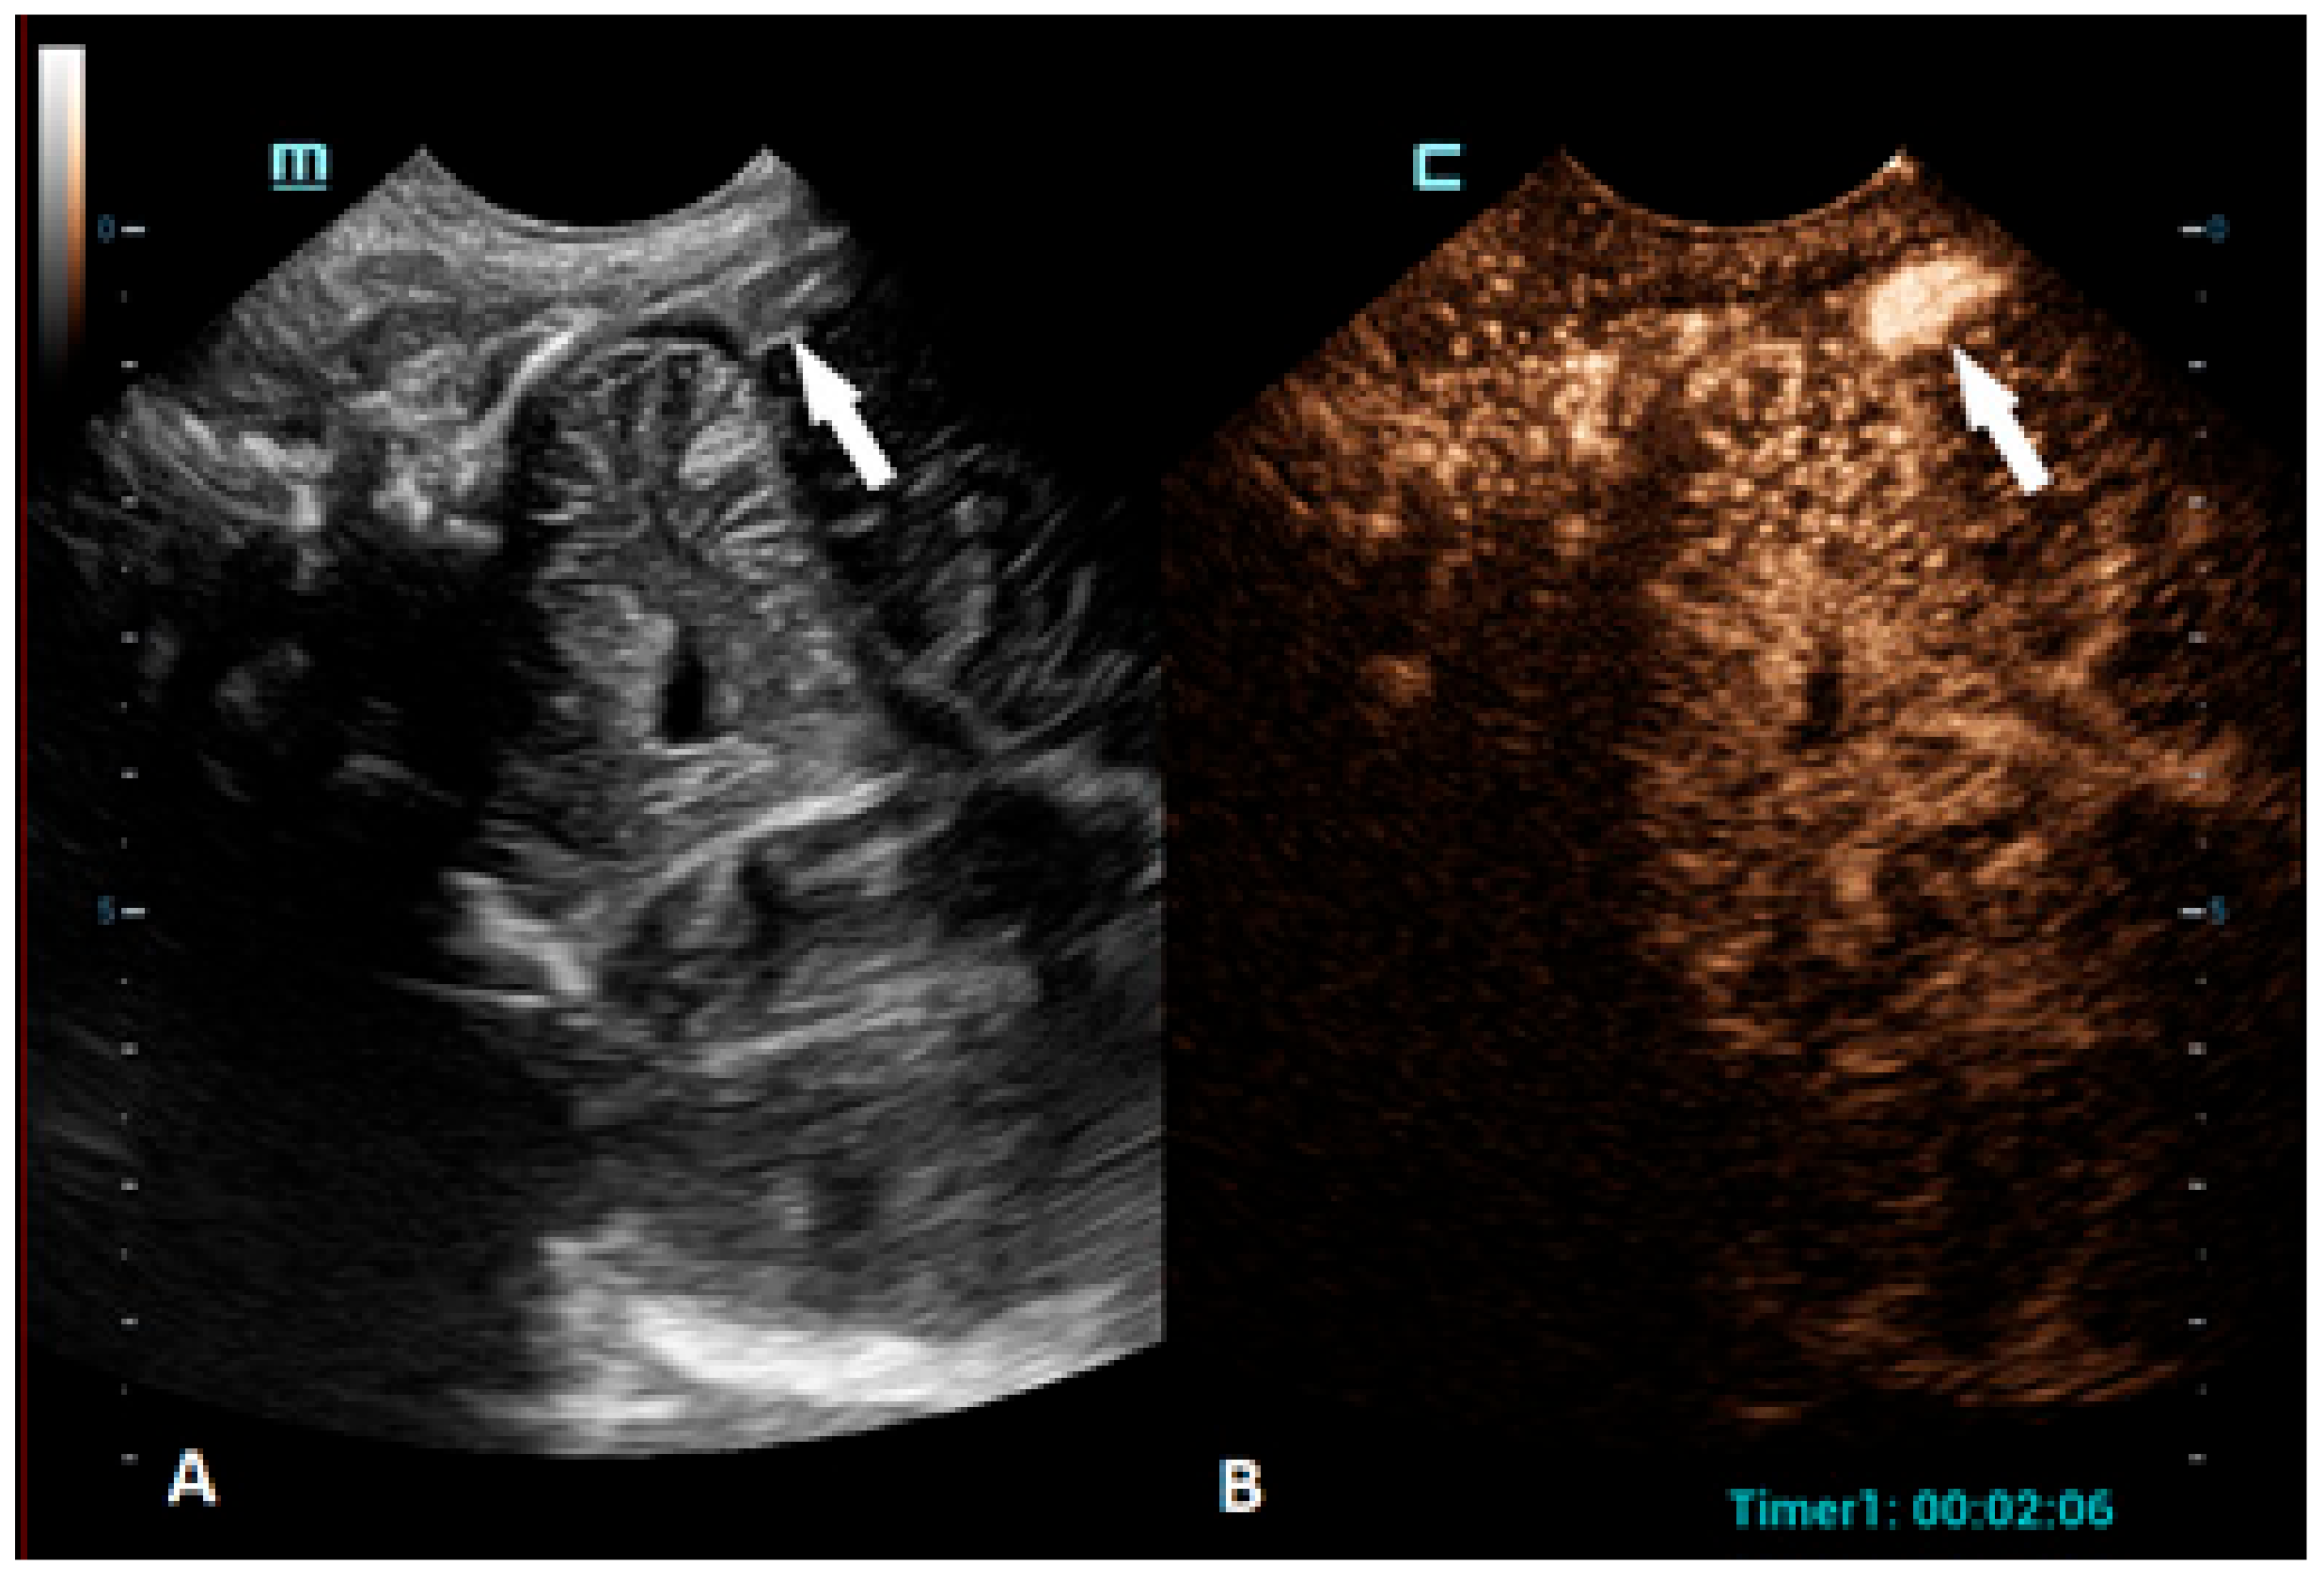

Figure 3.

A 1-day-old boy who presented with apnea. (A) The sagittal grayscale ultrasound brain image reveals a heterogeneous lesion (arrows) in the right frontotemporal region. (B) The sagittal CEUS image confirms avascularity of the lesion (arrowheads), consistent with the hemorrhage, and no obvious vascular malformation.